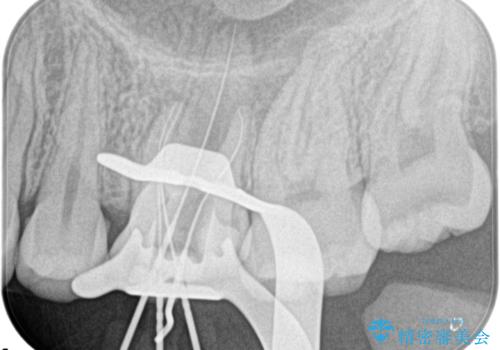

奥歯の根管治療

- 定期検診にて根尖に病変を認めた患者様です。

歯髄壊死の診断にて根管治療を行っております。

- 精密根管治療(イニシャルケース,大臼歯):122,000円、ファイバーコア:22,000円費用は治療当時の料金となります